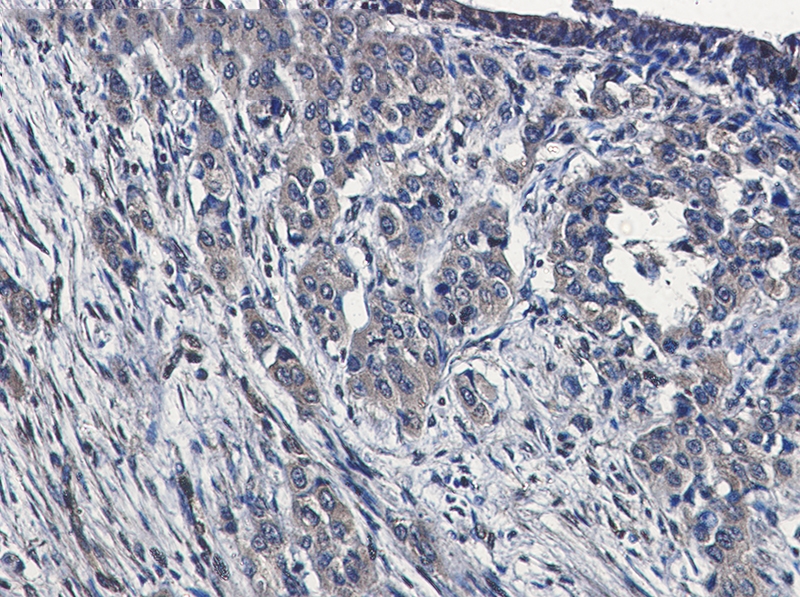

Immunohistochemistry of MAP3K4 in paraffin-embedded Human lung cancer tissue using MAP3K4 Rabbit mAb at dilution 1/50